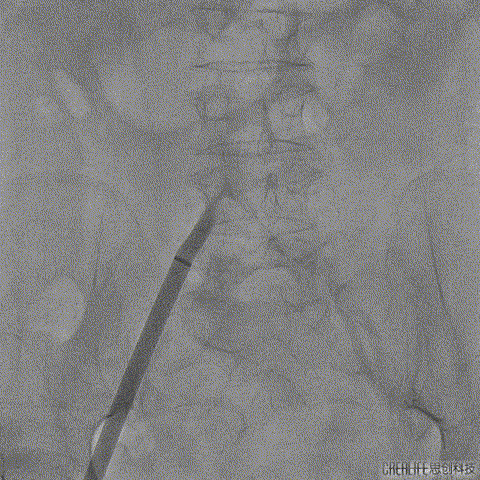

术前CT分析右侧的冠脉风险较高,球囊预扩前右冠开口处预放一个冠脉保护支架,采用18mm球囊预扩,有轻微腰征,无造影剂渗漏;

右侧冠脉保护准备

球囊预扩

TaurusElite输送系统轻松过弓、跨瓣,AV23瓣膜瓣环上约2mm释放;

TaurusElite轻松过弓

瓣膜释放